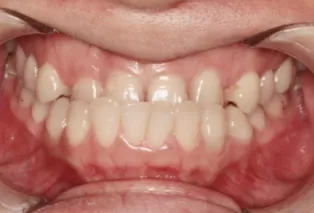

Intraoral photos